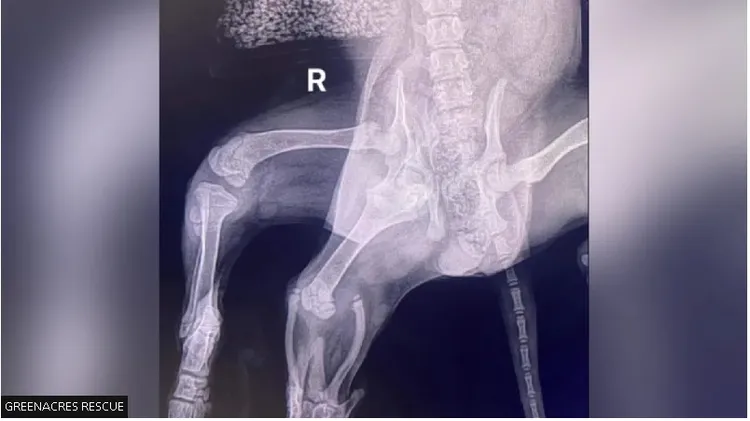

這隻目前已經4個多月大的狗狗,因為右邊屁股上多長了1對部分相連的腿,看起來就像小美人魚的尾巴,所以被取名為「愛麗兒」(Ariel)。

獸醫發現愛麗兒不僅比一般的狗多了2條腿,還多了1個外陰部,電腦斷層更發現牠只有1顆腎臟,提高手術的複雜程度。主刀獸醫指出:「因為愛麗兒右後腿有2個髖關節,所以牠的骨盆形狀也不對,導致牠那隻正常的右後腳沒有肌肉張力,我們擔心開刀可能會導致那隻正常的右後腳掉下來,幸好牠的情況在過去幾個月內有所改善。牠在手術後恢復得很好,現在過得很快樂,我們希望牠可以過很棒的狗生。」